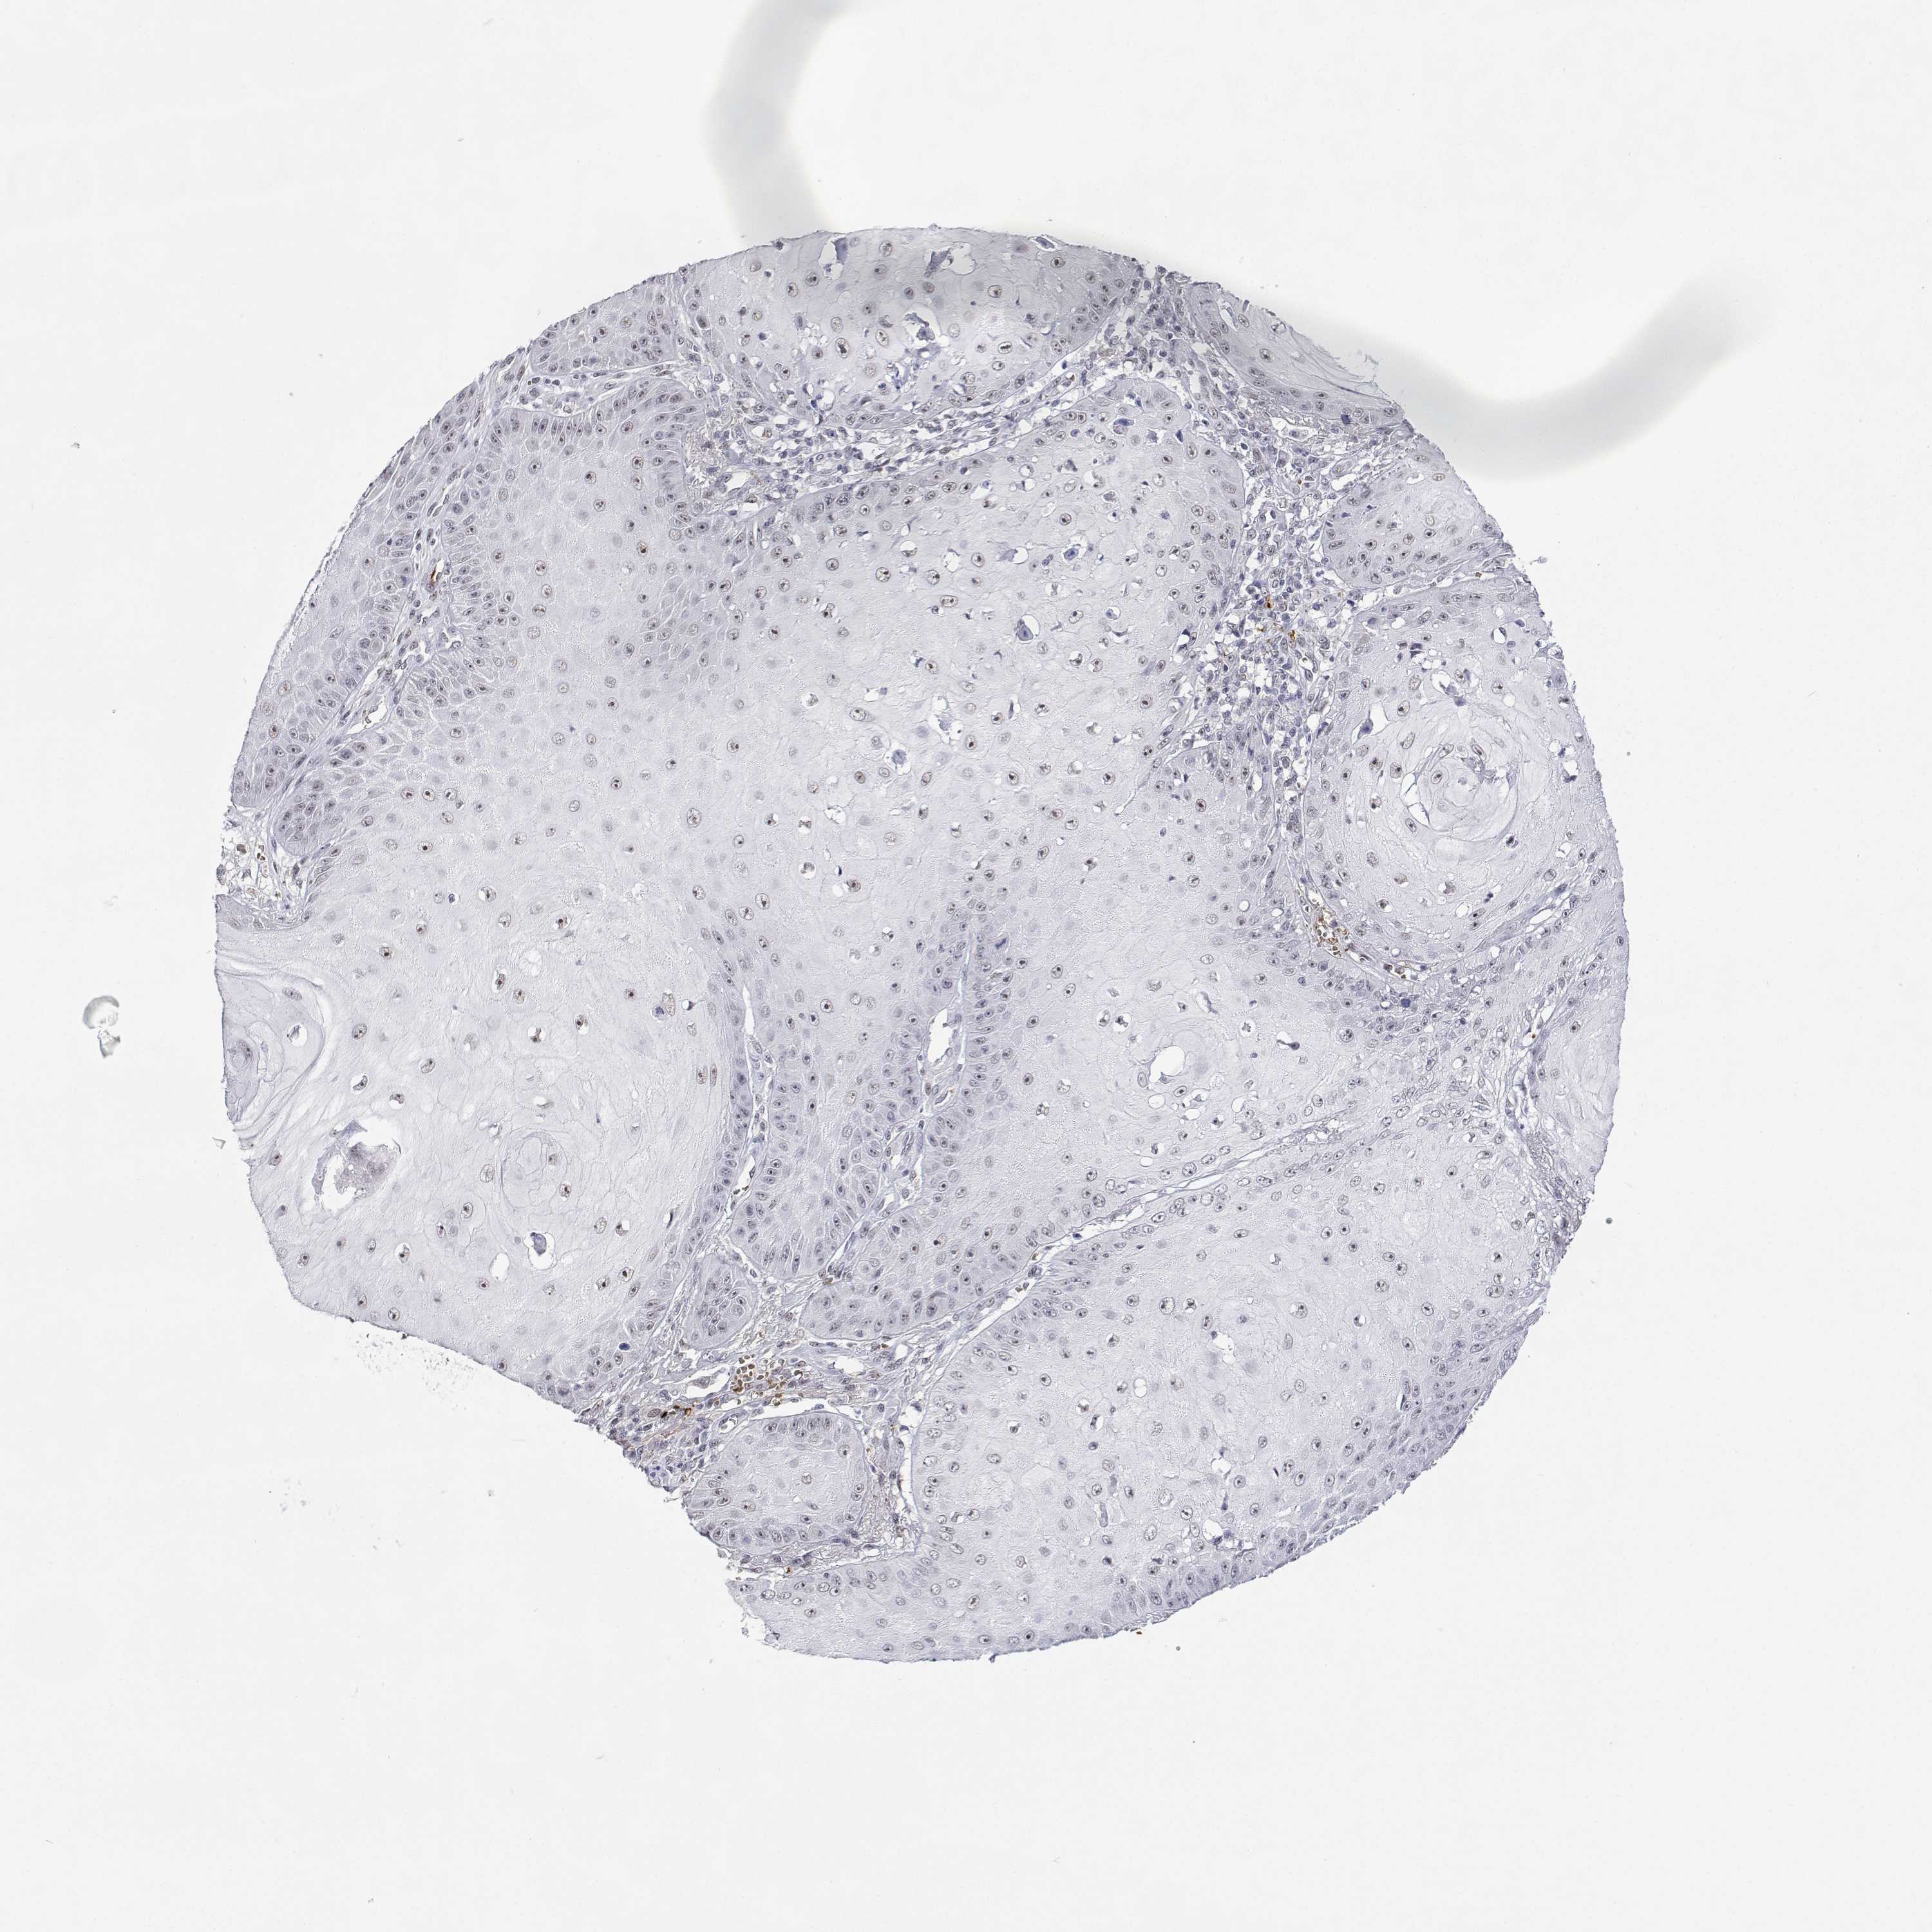

CANCER SKIN CANCER Show tissue menu

Basal cell and squamous cell cancer

SKIN CANCER - Protein expressioni

A mouse-over function shows sample information and annotation data. Click on an image to view it in a full screen mode. Samples can be filtered based on level of antibody staining by selecting one or several of the following categories: high, medium, low and not detected. The assay and annotation is described here.

Each image is clickable and will lead to virtual microscopy that enables deeper exploration of all samples and also displays staining intensity scores, fraction scores and subcellular localization as well as patient and tissue information for each sample.

Antibody HPA003890

Basal cell carcinoma

BCC, high aggressive

Squamous cell carcinoma, NOS

Squamous cell carcinoma, metastatic, NOS